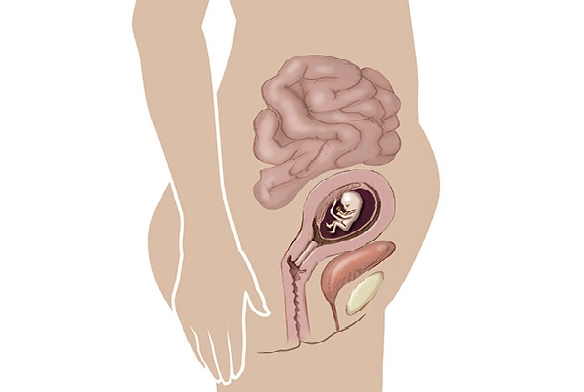

در هفته یازدهم بارداری، جنین شما تقریباً ۴۱ میلیمتر طول دارد؛ یعنی به اندازهی یک انجیر کوچک! 👶

در این مرحله، سر جنین هنوز نسبت به بدن بزرگتر است، اما بدنش بهسرعت در حال رشد و شکلگیری است.

در هفته یازدهم بارداری، جنین شما وارد مرحلهای شگفتانگیز از رشد و حرکت میشود. او حالا میتواند دورههای کوتاهی از خواب و بیداری را تجربه کند — معمولاً بین ۵ تا ۱۰ دقیقه. حتی ممکن است با سرفه یا حرکت ناگهانی شما بیدار شود!

در این هفته، بدن، دستها و پاهای جنین سریعتر از سرش رشد میکنند و ظاهر او بیش از پیش به یک انسان کوچک واقعی شبیه میشود.

در هفته یازدهم بارداری، رحم شما بهسرعت در حال رشد است و لگن برای ایجاد فضای کافی بهتدریج گشادتر میشود. همین موضوع میتواند باعث بروز درد و کشیدگی در ناحیه بین ناف و کشاله ران شود.